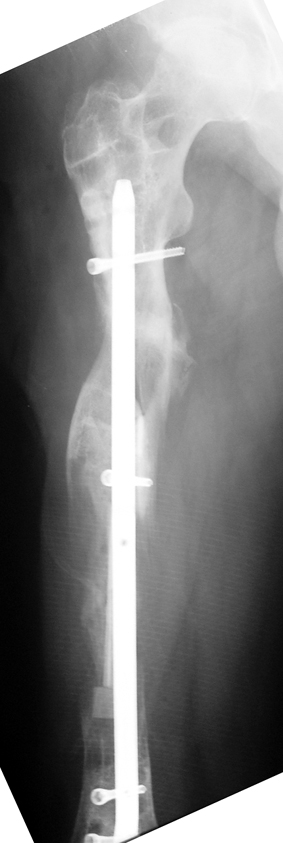

The duration of external fixation (external fixation index) depends on the amount of distraction required, and the extremity is prone to complications during this period. After the distraction phase is completed, the external fixator remains in place during the consolidation phase, which lasts twice as long as the distraction phase; but this period is hardly tolerated. If the external fixator is removed before sufficient consolidation is achieved, fractures, deformity and shortness will be the result. In our department, ‘lenghthening over nail’ method is used in order to decrease the external fixation index and increase patient comfort and activity level. In this method, the intramedullary nail is statically locked after the completion of the distraction phase, and external fixator is removed. The extremity is stabilized by the intramedullary nail during consolidation phase. In this way, complications due to long external fixation index or early removal of the external fixator are avoided.

Case 1